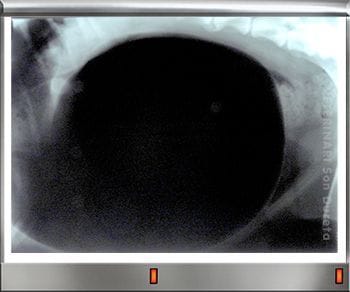

Rápidamente lo trajeron al Servicio Veterinario de Urgencias de la Clínica Veterinaria Son Dureta. Pancho llegó con un shock hipovolémico, (falta de oxígeno en órganos y tejidos debido a la pérdida tan grande y aguda de líquidos y sangre) sus mucosas estaban muy pálidas, su pulso era débil y su temperatura corporal muy baja. Se realizaron analíticas, donde no se identificaron órganos internos dañados aunque las enzimas hepáticas estaban alteradas y por supuesto, las alteraciones del sistema digestivo asociadas a su estado.

Pancho requería una actuación veterinaria intensiva y urgente, inmediatamente se administraron fluidos por vía intravenosa y una transfusión de plasma, con el objetivo de corregir su deshidratación, coagulación y restaurar su volumen de líquido circulante. Le aplicamos calor para recuperar su temperatura corporal y toda la medicación de apoyo necesaria para ayudar a su estómago e intestinos a recuperarse (protectores gástricos, antibióticos, analgésicos, protectores hepáticos y vitaminas).